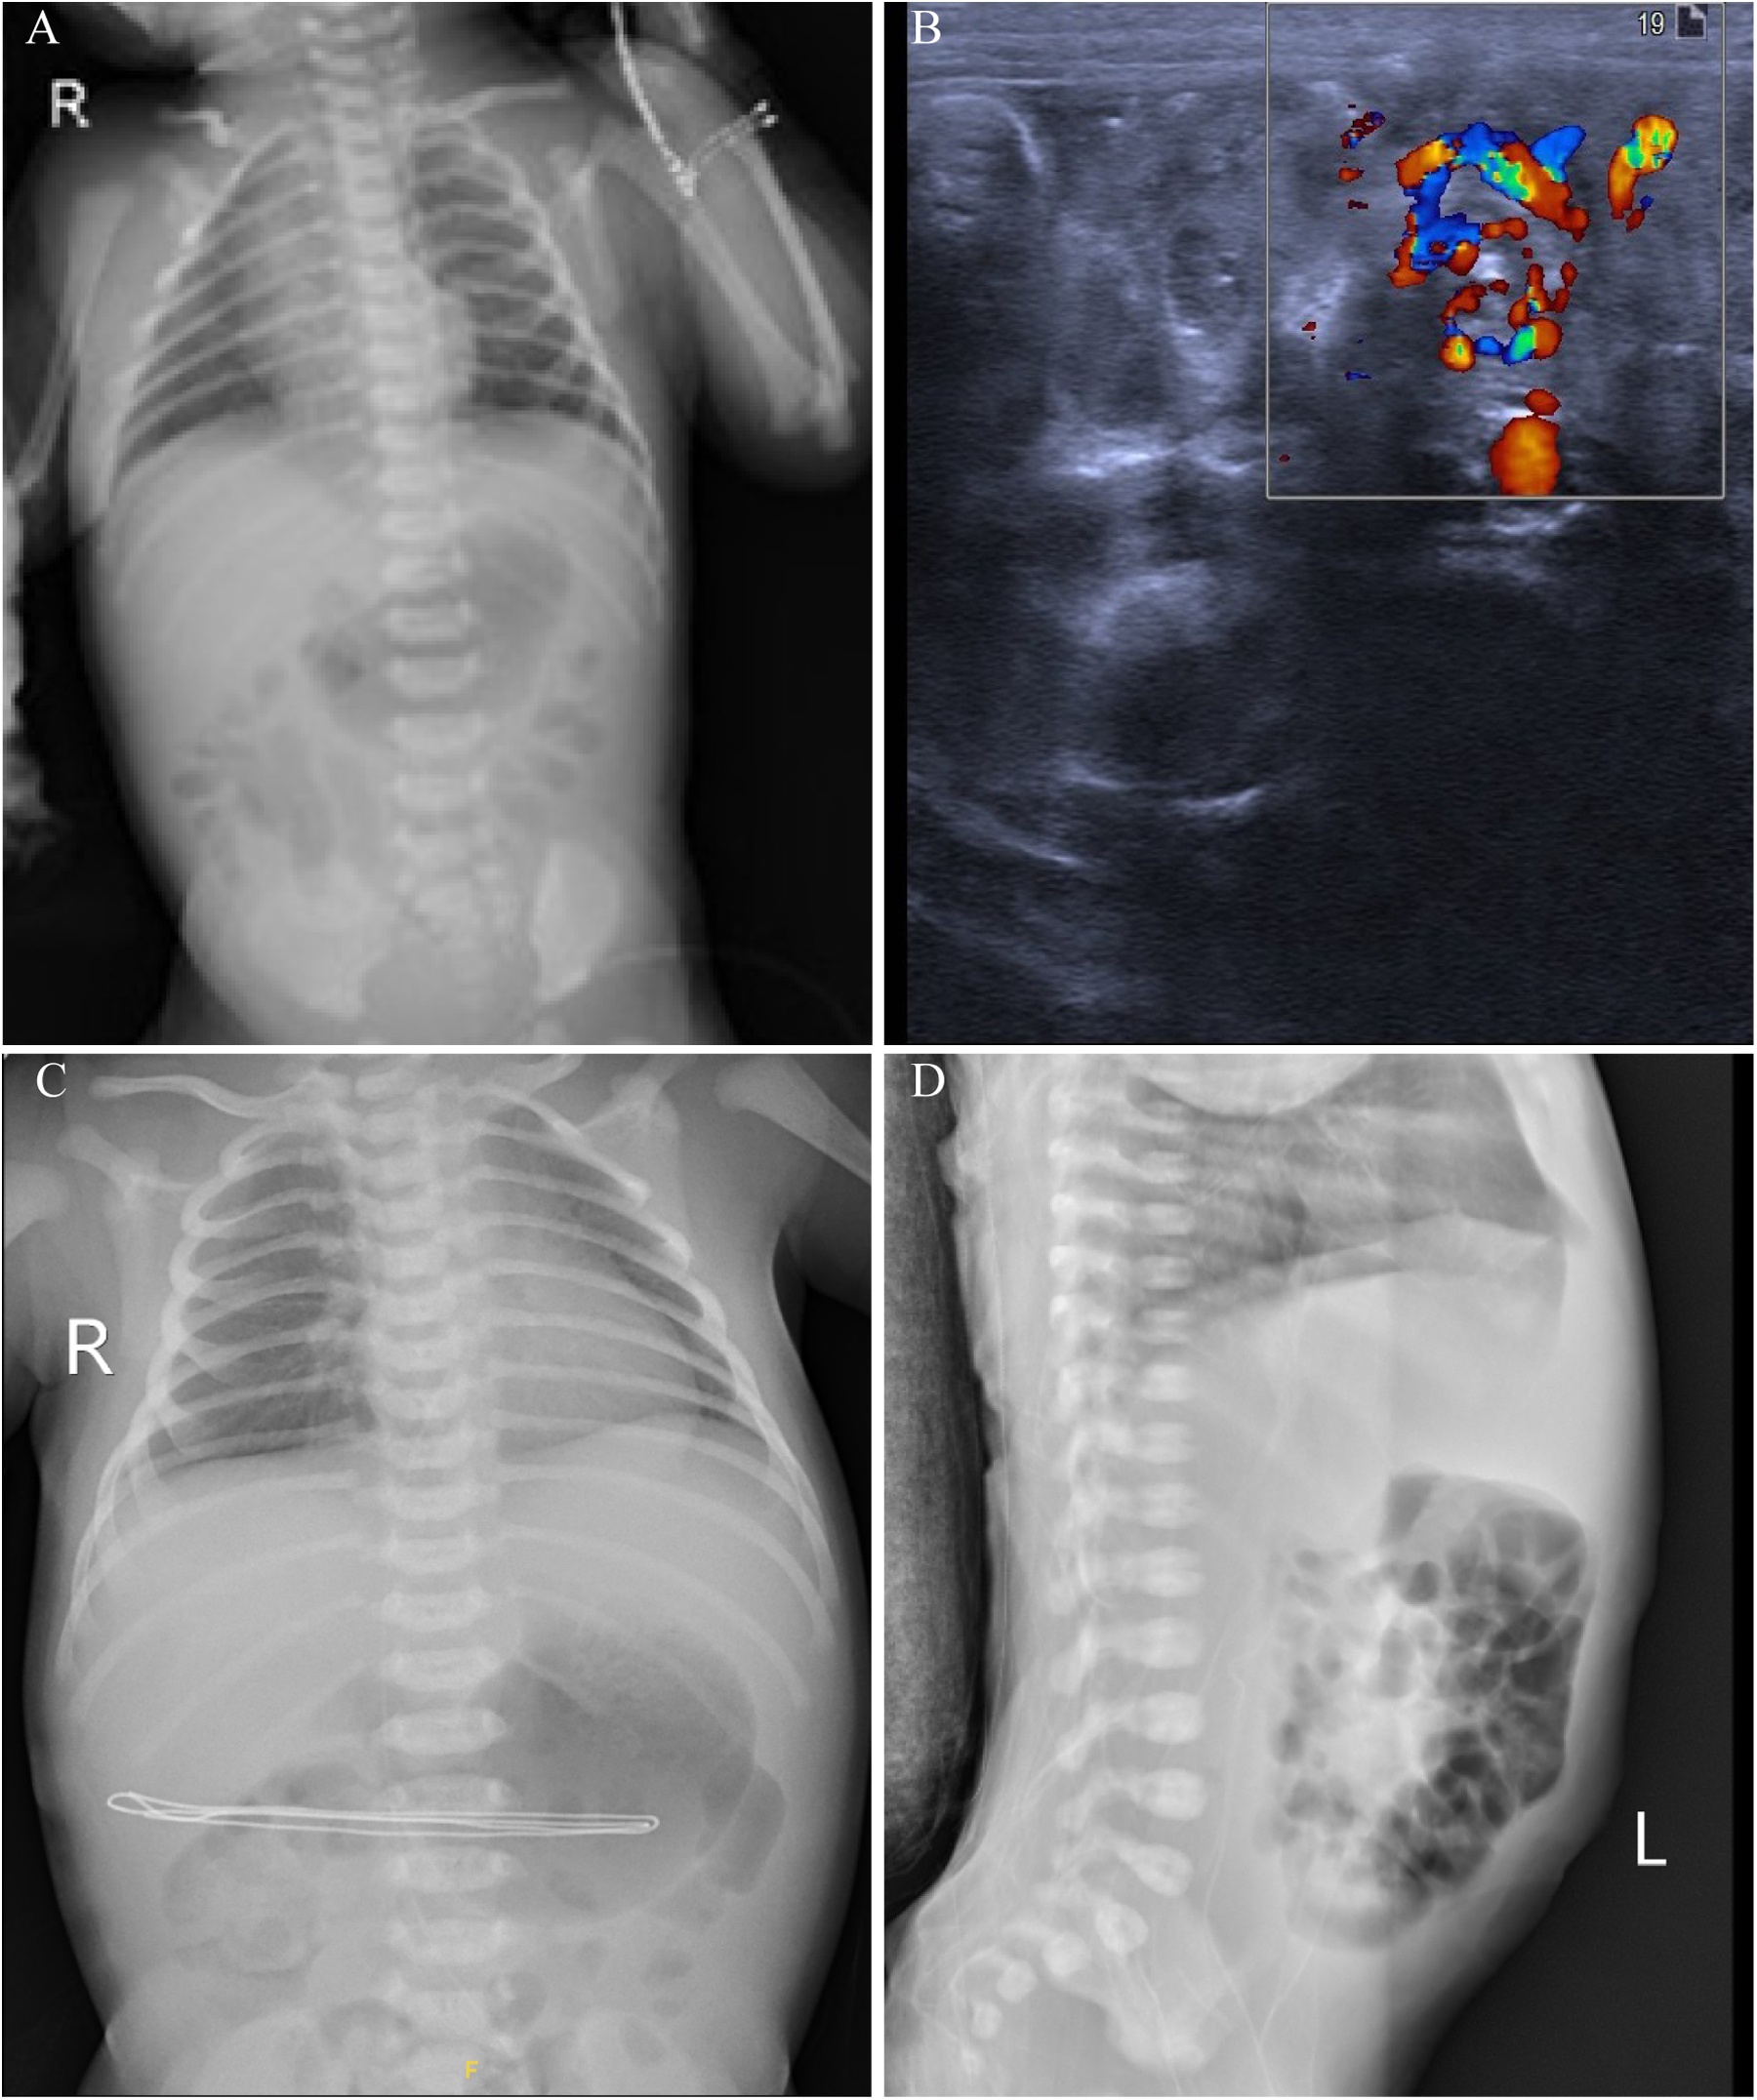

Diagnostic tests revealed a blood gas analysis showing a pH of 7.41, sodium 139.4 mmol/L, calcium 1.17 mmol/L, pCO2 24.2 mmHg, pO2 52.5 mmHg, bicarbonate 14.9 mmol/L, base excess −7.28 mmol/L, blood glucose 5.5 mmol/L, lactate 4.6 mmol/L, and hemoglobin 17.7 g/dl, indicating elevated lactate and negative base excess. The patient received a 30 ml normal saline infusion for volume expansion. Complete blood count (CBC), C-reactive protein (CRP) and coagulation function tests showed no significant issues. Upon admission, the neonate passed a large amount of bright red bloody stool and vomited coffee-colored material. The stool occult blood test was positive (+++). An abdominal x-ray showed gas in the small intestine and colon (Figure 1A), while an ultrasound revealed a mixed mass in the upper abdomen with a “whirlpool sign,” measuring about 21 mm × 18 mm (Figure 1B). Intestinal malrotation was suspected, and the patient was transferred to a tertiary hospital. After ruling out contraindications, the patient underwent an open Ladd's procedure with appendectomy. The surgery was uneventful, revealing approximately 10 ml of brownish fluid in the abdominal cavity, which was sent for culture. The mesenteric root was twisted 480 degrees clockwise, causing midgut volvulus; the small intestine was slightly dark but normalized after untwisting. Immediate fluid resuscitation with crystalloids was initiated intraoperatively to address third-space losses and potential reperfusion injury following untwisting. Hemodynamic parameters were closely monitored, and the patient remained stable throughout the procedure. The surgery was successful, and the patient received antibiotics and nutritional support postoperatively. By the second postoperative day, bedside x-rays showed increased gas in the small intestine and colon compared to preoperative levels (Figure 1C). Subsequently, on the fourth postoperative day, a lateral abdominal radiograph revealed significant intraluminal gas (Figure 1D).

Figure 1. Imaging findings of a 2-day-old neonate with intestinal malrotation. (A) Chest and abdominal x-rays show scattered gas in the small intestine and colon, indicating possible gastrointestinal obstruction. (B) Abdominal ultrasound reveals the whirlpool sign, with the superior mesenteric vein rotating around the superior mesenteric artery. (C) Postoperative x-rays show increased gas in the small intestine and colon on the second postoperative day compared to preoperative levels. (D) A lateral abdominal radiograph on the fourth postoperative day shows significant intraluminal gas.